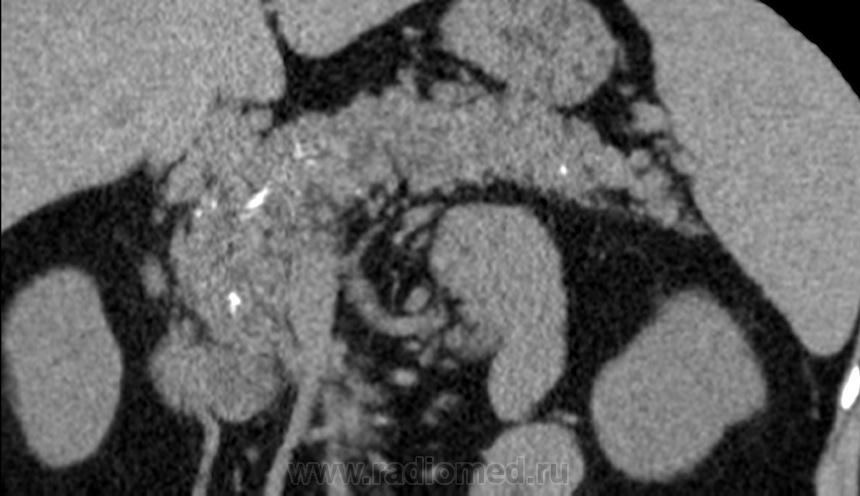

Итак пациент мужчина 34 года, в анамнезе - 16 эпизодов острого панкреатита (!). Пациенту была выполнена ЭРХПГ которая выявила наличие двух стриктур протока Вирсунга в области головки поджелудочной железы (доброкачественная стриктура Вирсунгова протока). На представленных мной изображениях определяется неоднородная структура поджелудочной железы с гиподенсными участками в области тела/хвоста и наличием паренхиматозных кальцификатов (b & c). Такая картина указывает на хронический панкреатит. В области головки визуализируется стент (a), установленный в Вирсунгов проток, с свободным концом в просвете 12-ти перстной кишки. Такое стояние стента является правильным. На данный момент, единственной адекватной терапией при доброкачественных стриктурах протока поджелудочной железы (и при некоторых опухолях исходящим из протока или обтурирующих его, когда невозможно выполнить резекцию) является эндоскопическое стентирование протока, что обеспечивает нормальный отток секрета поджелудочной в кишечник.